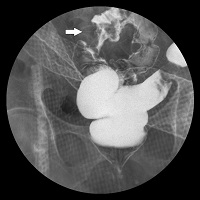

대장암의 대장이중조영검사 소견 이미지

[대장암의 대장이중조영검사 소견]